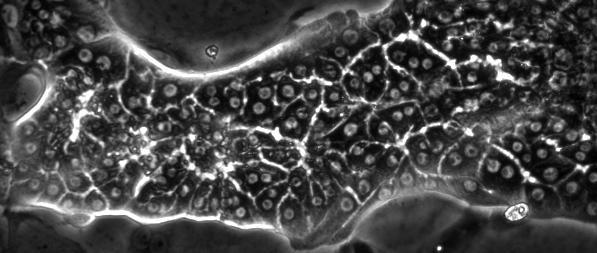

Meanwhile, fluid dynamics is also being applied in the field of regenerative medicine, a topic of much discussion today. Figure 2 shows a capillary network formed by the endothelial cells that constitute the inner wall of a blood vessel. A branch-like structure is visible in the center of the photograph; this is the capillary network. It has been found that this capillary network grows in response to the stimulus of force from blood flow on the vessel wall (in the background, you can see what looks like paving stones; these are the endothelial cells of the vessel wall). In other words, the endothelial cells of the blood vessel sense the blood flow and attempt to expand the capillary network. We are working hard to utilize this property to form capillary networks within regenerated organs. Figure 3 is a micrograph showing bile canaliculi of the liver, formed in vitro, contracting to pump out bile.